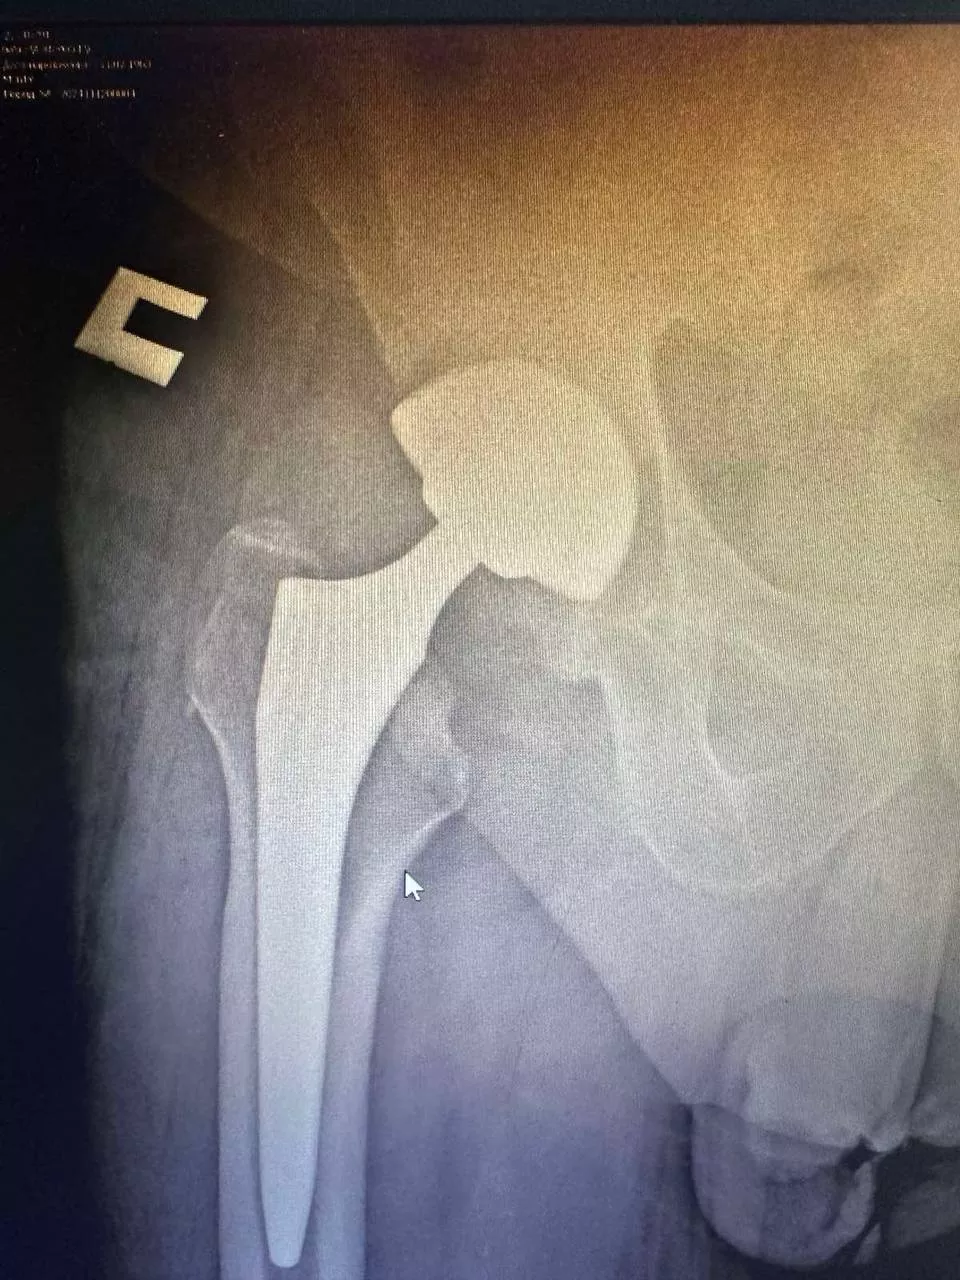

Ендопротезування кульшового суглоба

Заміна кульшового суглоба — одна з найефективніших операцій, яка вважається "золотим стандартом" в ортопедії. Цей вид хірургічного втручання виконується для лікування важких захворювань суглобів і відновлення їхньої рухливості. Під час операції пошкоджений суглоб замінюється на штучний імплантат, що дає змогу значно зменшити біль і повернути свободу рухів. Ендопротезування допомагає відновити повноцінне функціонування кульшового суглоба, забезпечуючи пацієнту активне і комфортне життя.

Ендопротезування кульшового суглоба — оптимальний варіант для пацієнтів із серйозними ушкодженнями кульшового суглоба, спричиненими артрозом, травмами або запаленнями. Операція допомагає усунути біль і повернути рухливість, даючи змогу пацієнтові вести активний спосіб життя.